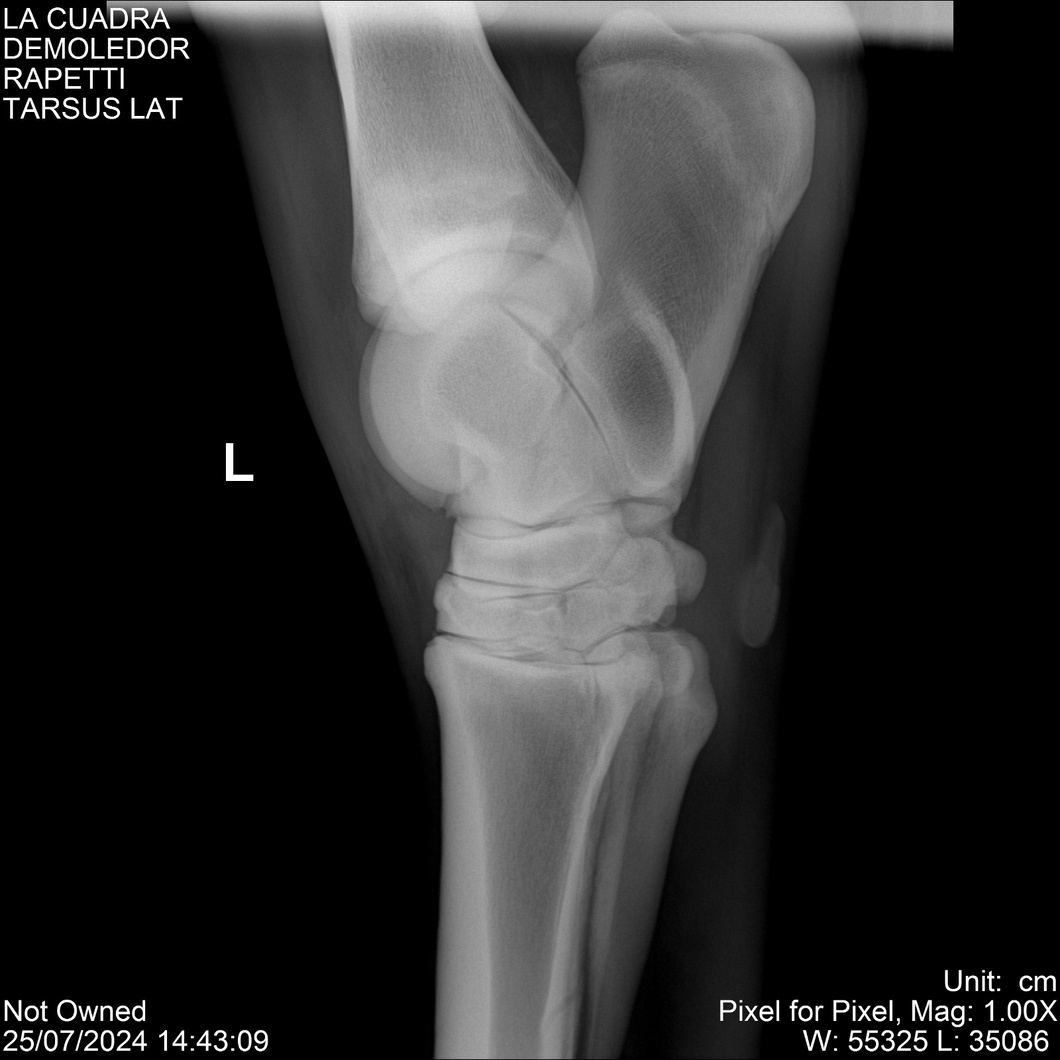

LOTE 14, DEMOLEDOR 🔥 🔥 🔥 Lote Anterior Volver al remate Lote Siguiente Ficha Contacto Montevideo - Ficha del Lote Identificador: #284454 Categoría: Yeguarizos Montevideo - 89 Visualizaciones ClicData Contacto Empresa: Abelenda N. R., Walter Hugo Nombre*: Teléfono* : E-mail* : Mensaje Enviar Registrese gratis Este contenido Exclusivo está disponible sólo para usuarios registrados Ingresar